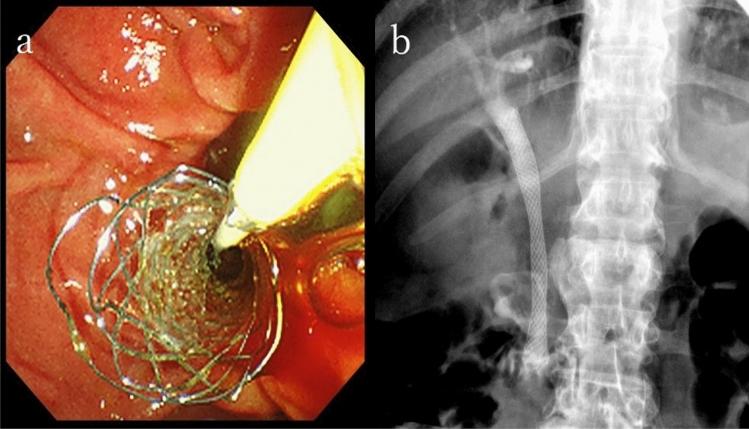

We present the case of an 86-year-old man who had undergone left nephrectomy for renal cell carcinoma (clear cell carcinoma) 22 years ago. He visited the emergency department complaining of right hypochondrial pain and fever. He was eventually diagnosed with acute cholangitis. Abdominal contrast-enhanced computed tomography showed multiple tumors in the pancreas. The tumor in the pancreatic head obstructed the distal bile duct. Endoscopic retrograde cholangiopancreatography detected bloody bile juice flowing from the papilla of Vater. Therefore, he was diagnosed with hemobilia. Cholangiography showed extrinsic compression of the distal bile duct; a 6 Fr endoscopic nasobiliary drainage tube was placed. Endoscopic ultrasound showed that the pancreas contained multiple well-defined hypoechoic masses. Endoscopic ultrasound-guided fine-needle aspiration was performed using a 22 G needle. Pathological examination revealed clear cell carcinoma, and the final diagnosis was pancreatic metastasis of renal cell carcinoma (RCC) causing hemobilia. A partially covered metallic stent was placed in the distal bile duct. Consequently, hemobilia and cholangitis were resolved.

我们报告了一例 86 岁男性病例,他 22 年前因肾细胞癌(透明细胞癌)行左肾切除术。他因右季肋部疼痛和发热就诊于急诊科。最终被诊断为急性胆管炎。腹部增强 CT 显示胰腺内有多发性肿瘤。胰头部的肿瘤阻塞了远端胆管。内镜逆行胰胆管造影(ERCP)发现从 Vater 乳头流出血性胆汁。因此,他被诊断为胆血症。胆管造影显示远端胆管受到外压性狭窄;放置了一根 6Fr 的鼻胆管引流管。内镜超声显示胰腺内有多个边界清晰的低回声肿块。使用 22G 针进行了内镜超声引导下细针抽吸。病理检查显示为透明细胞癌,最终诊断为肾细胞癌(RCC)胰腺转移导致胆血症。在远端胆管内放置了一枚部分覆膜的金属支架。随后,胆血症和胆管炎得到解决。